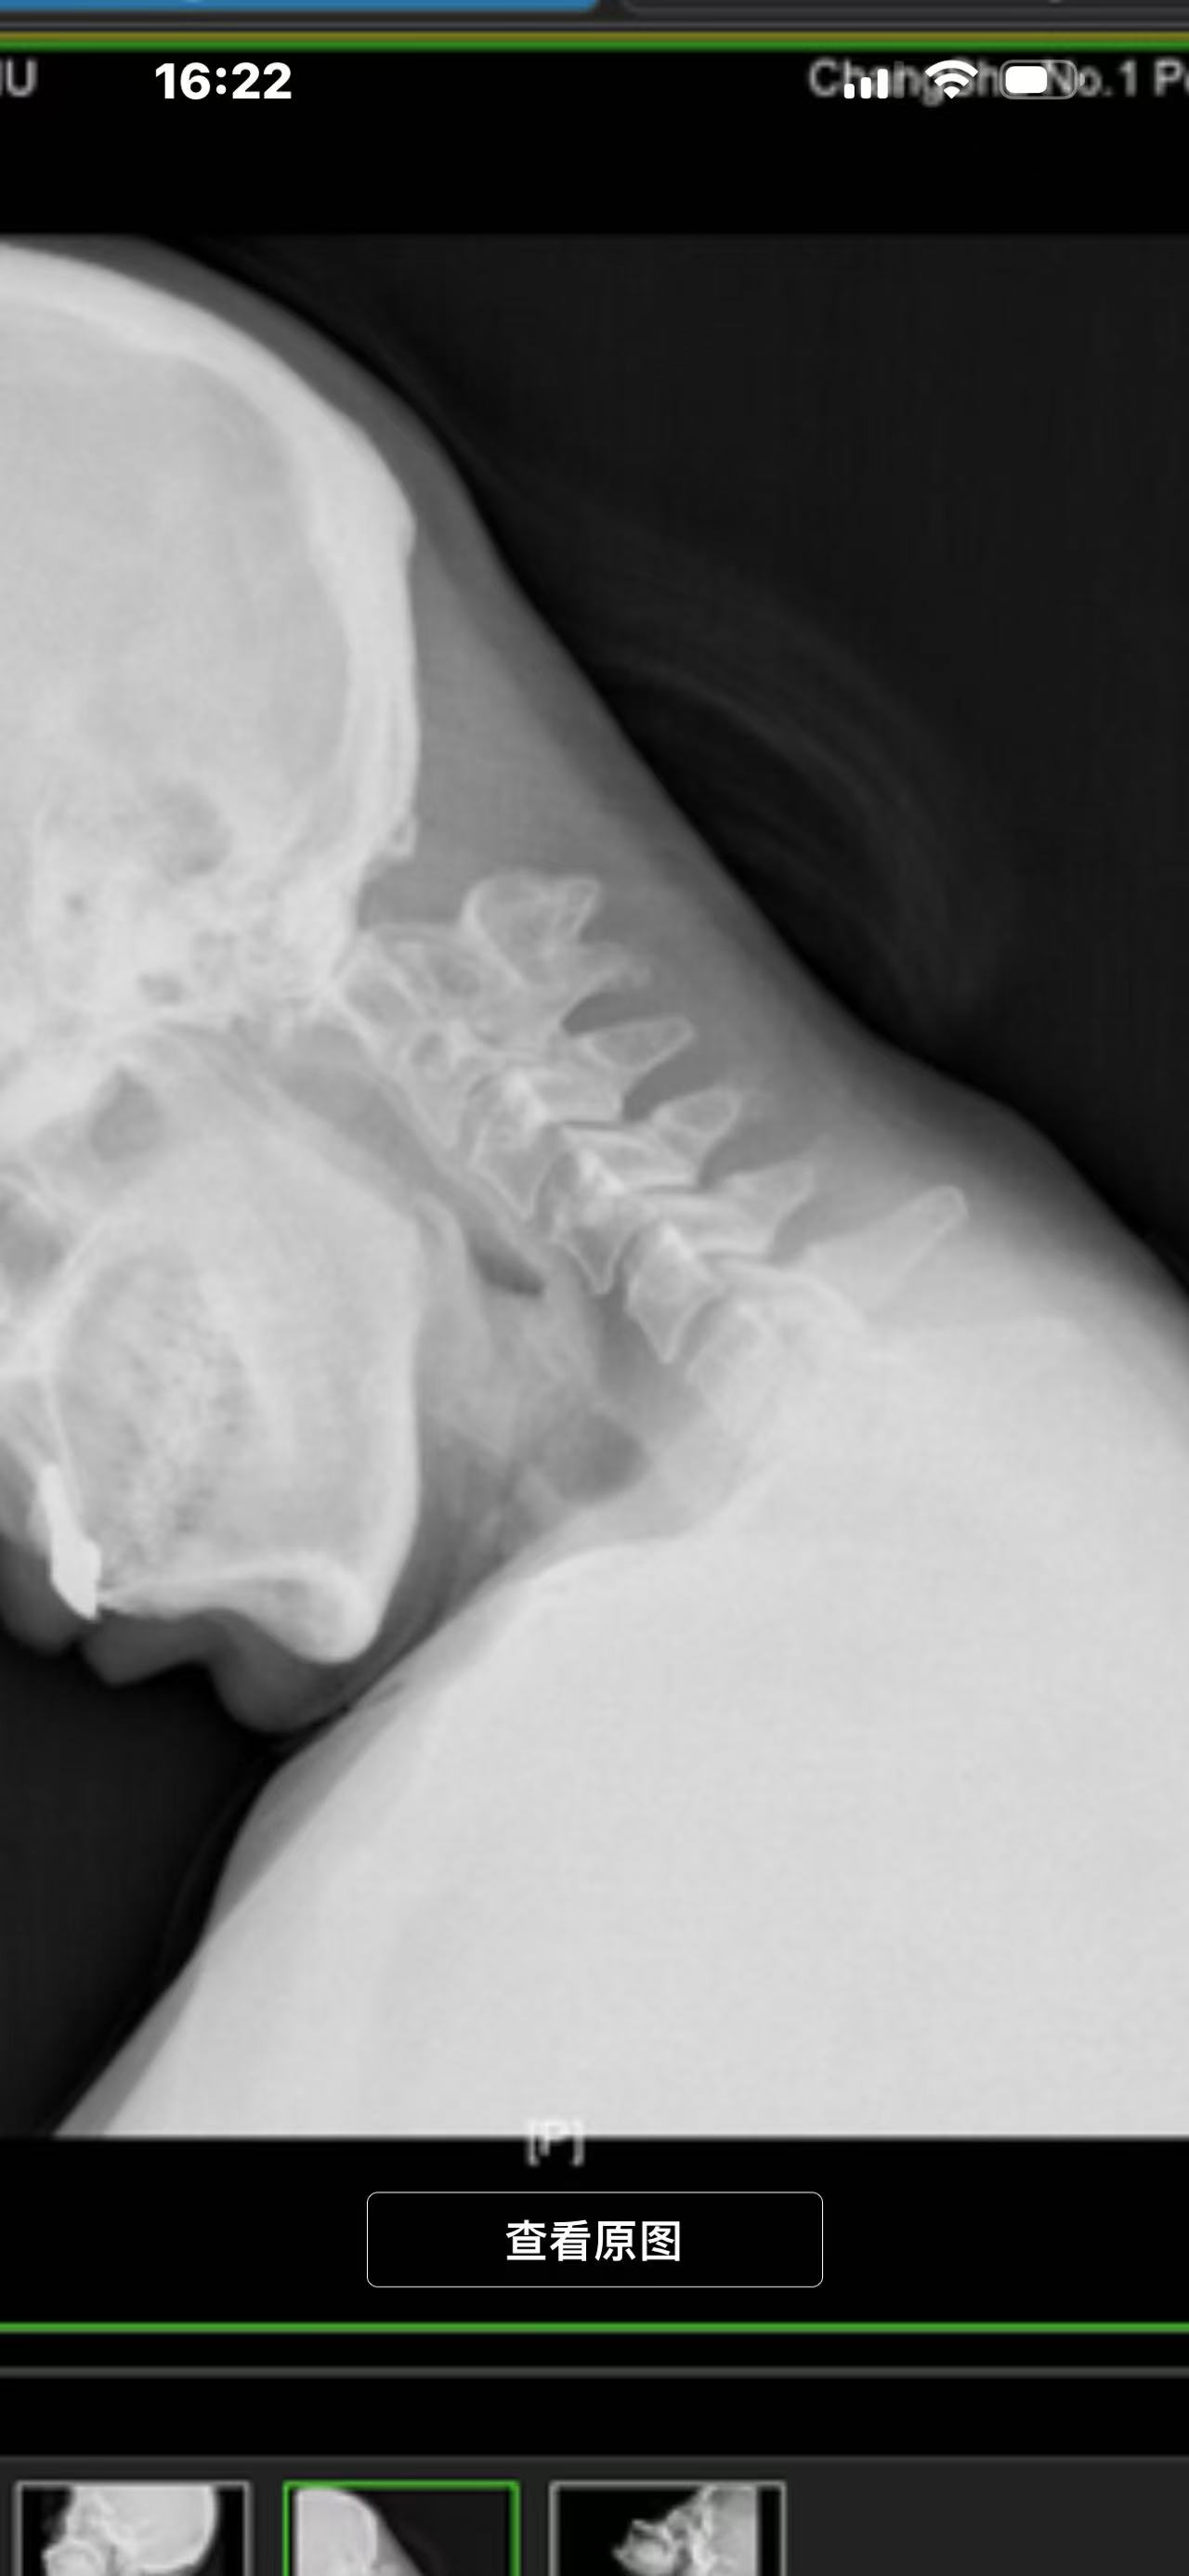

• 诊断:寰枢椎脱位,颅底凹陷

• 影像: